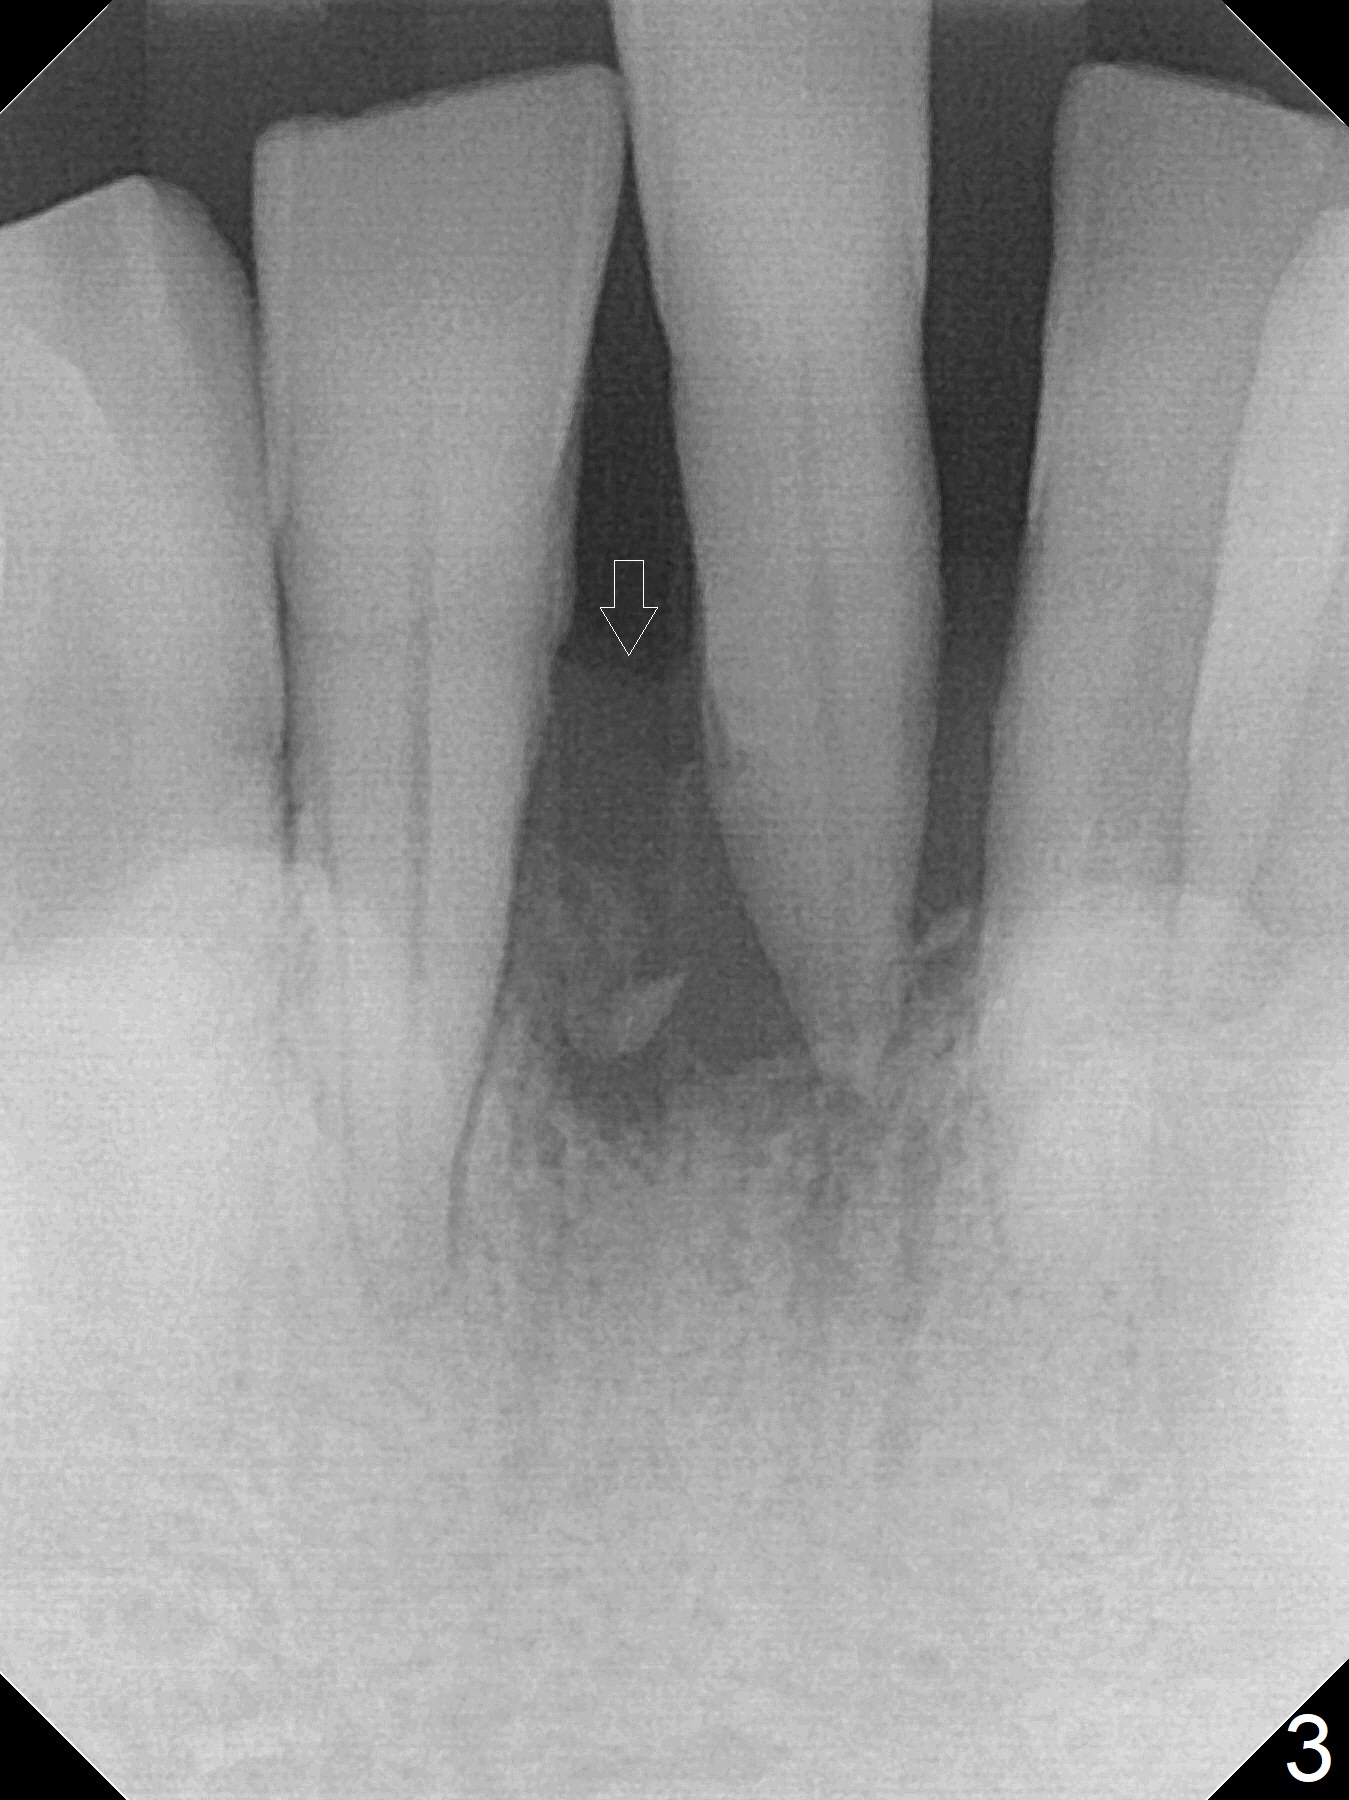

When the patient returns for implant placement 1.5 years after the last treatment (SRP), the tooth #25 has exfoliated, whereas the tooth #24 is severely displaced (Fig.1-3).  In fact the buccolingual plates are found to be lost after extraction, corresponding to change in gingival color indicated by an arrowhead in Fig.1.  Initial osteotomy with 1.2 mm drill is parallel to the terminal branches of the Incisive Canal (Fig.4 arrowheads).  Since the gingiva is as thick as 7.5 mm (Fig.3 arrow), a 3x14 mm 1-piece implant with 4 mm cuff is placed (Fig.5); three implant threads are outside the native bone; with allograft (*) placed and the neighboring crests being coronal to the threads, the chance of periimplantitis should be remote.  An immediate provisional is fabricated to contain the graft in place.  Meanwhile the tooth #2 is symptomatic with crack.  The top 3 threads appear to be contacted by the newly formed crestal bone 6 months postop (Fig.6 *).  Bone appears to have grown into the space between implant threads 6 months post cementation (13 months postop).